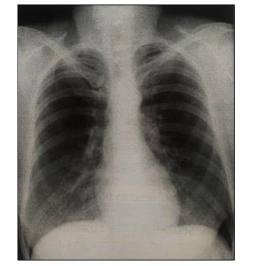

Na radiografia de tórax em PA é possível observar uma falha no posicionamento do paciente, o que causa uma distorção do tamanho de algumas estruturas no estudo:

Dessa forma, é possível afirmar que o critério não observado foi: